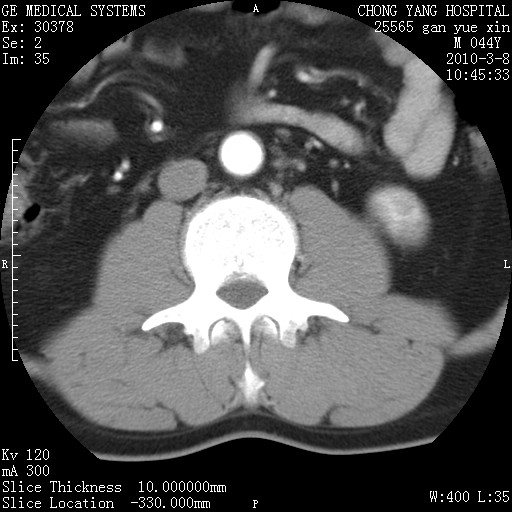

标题: CT24940:主动脉增强,典型病例。 [打印本页]

标题: CT24940:主动脉增强,典型病例。

夹层动脉瘤。

动脉夹层

夹层动脉瘤,典型

主动脉夹层。

动脉夹层的分型:

⒈debakey分型:根据主动脉夹层累及部位,分为三型:ⅰ型:原发破口位于升主动脉或主动脉弓部,夹层累及升主动脉、主动脉弓部、胸主动脉、腹主动脉大部或全部,少数可累及髂动脉。ⅱ型:原发破口位于升主动脉,夹层累及升主动脉,少数可累及部分主动脉弓。ⅲ型:原发破口位于左锁骨下动脉开口远端,根据夹层累及范围又分为ⅲa,ⅲb。ⅲa型:夹层累及胸主动脉。ⅲb型:夹层累及升主动脉、腹主动脉大部或全部。少数可累及髂动脉。

⒉stanford分型:a型:夹层累及升主动脉,无论远端范围如何。b型:夹层累及左锁骨下动脉开口以远的降主动脉。

夹层动脉瘤,少量胸水

夹层动脉瘤;左侧少量胸腔积液。

典型主动脉夹层。